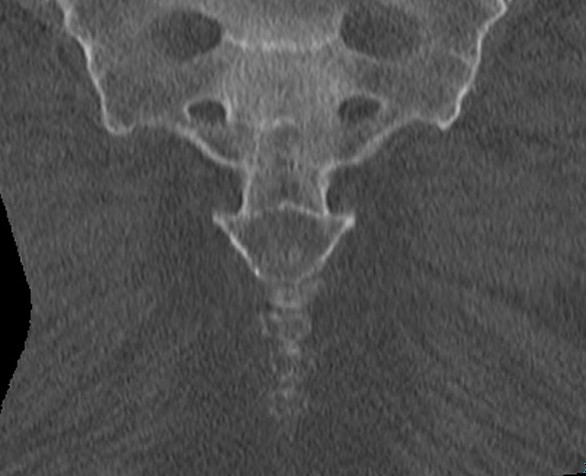

Anatomy

3 or 4 fused coccygeal vertebrae

Triangular structure

Usually a joint with sacrum

- can be fused